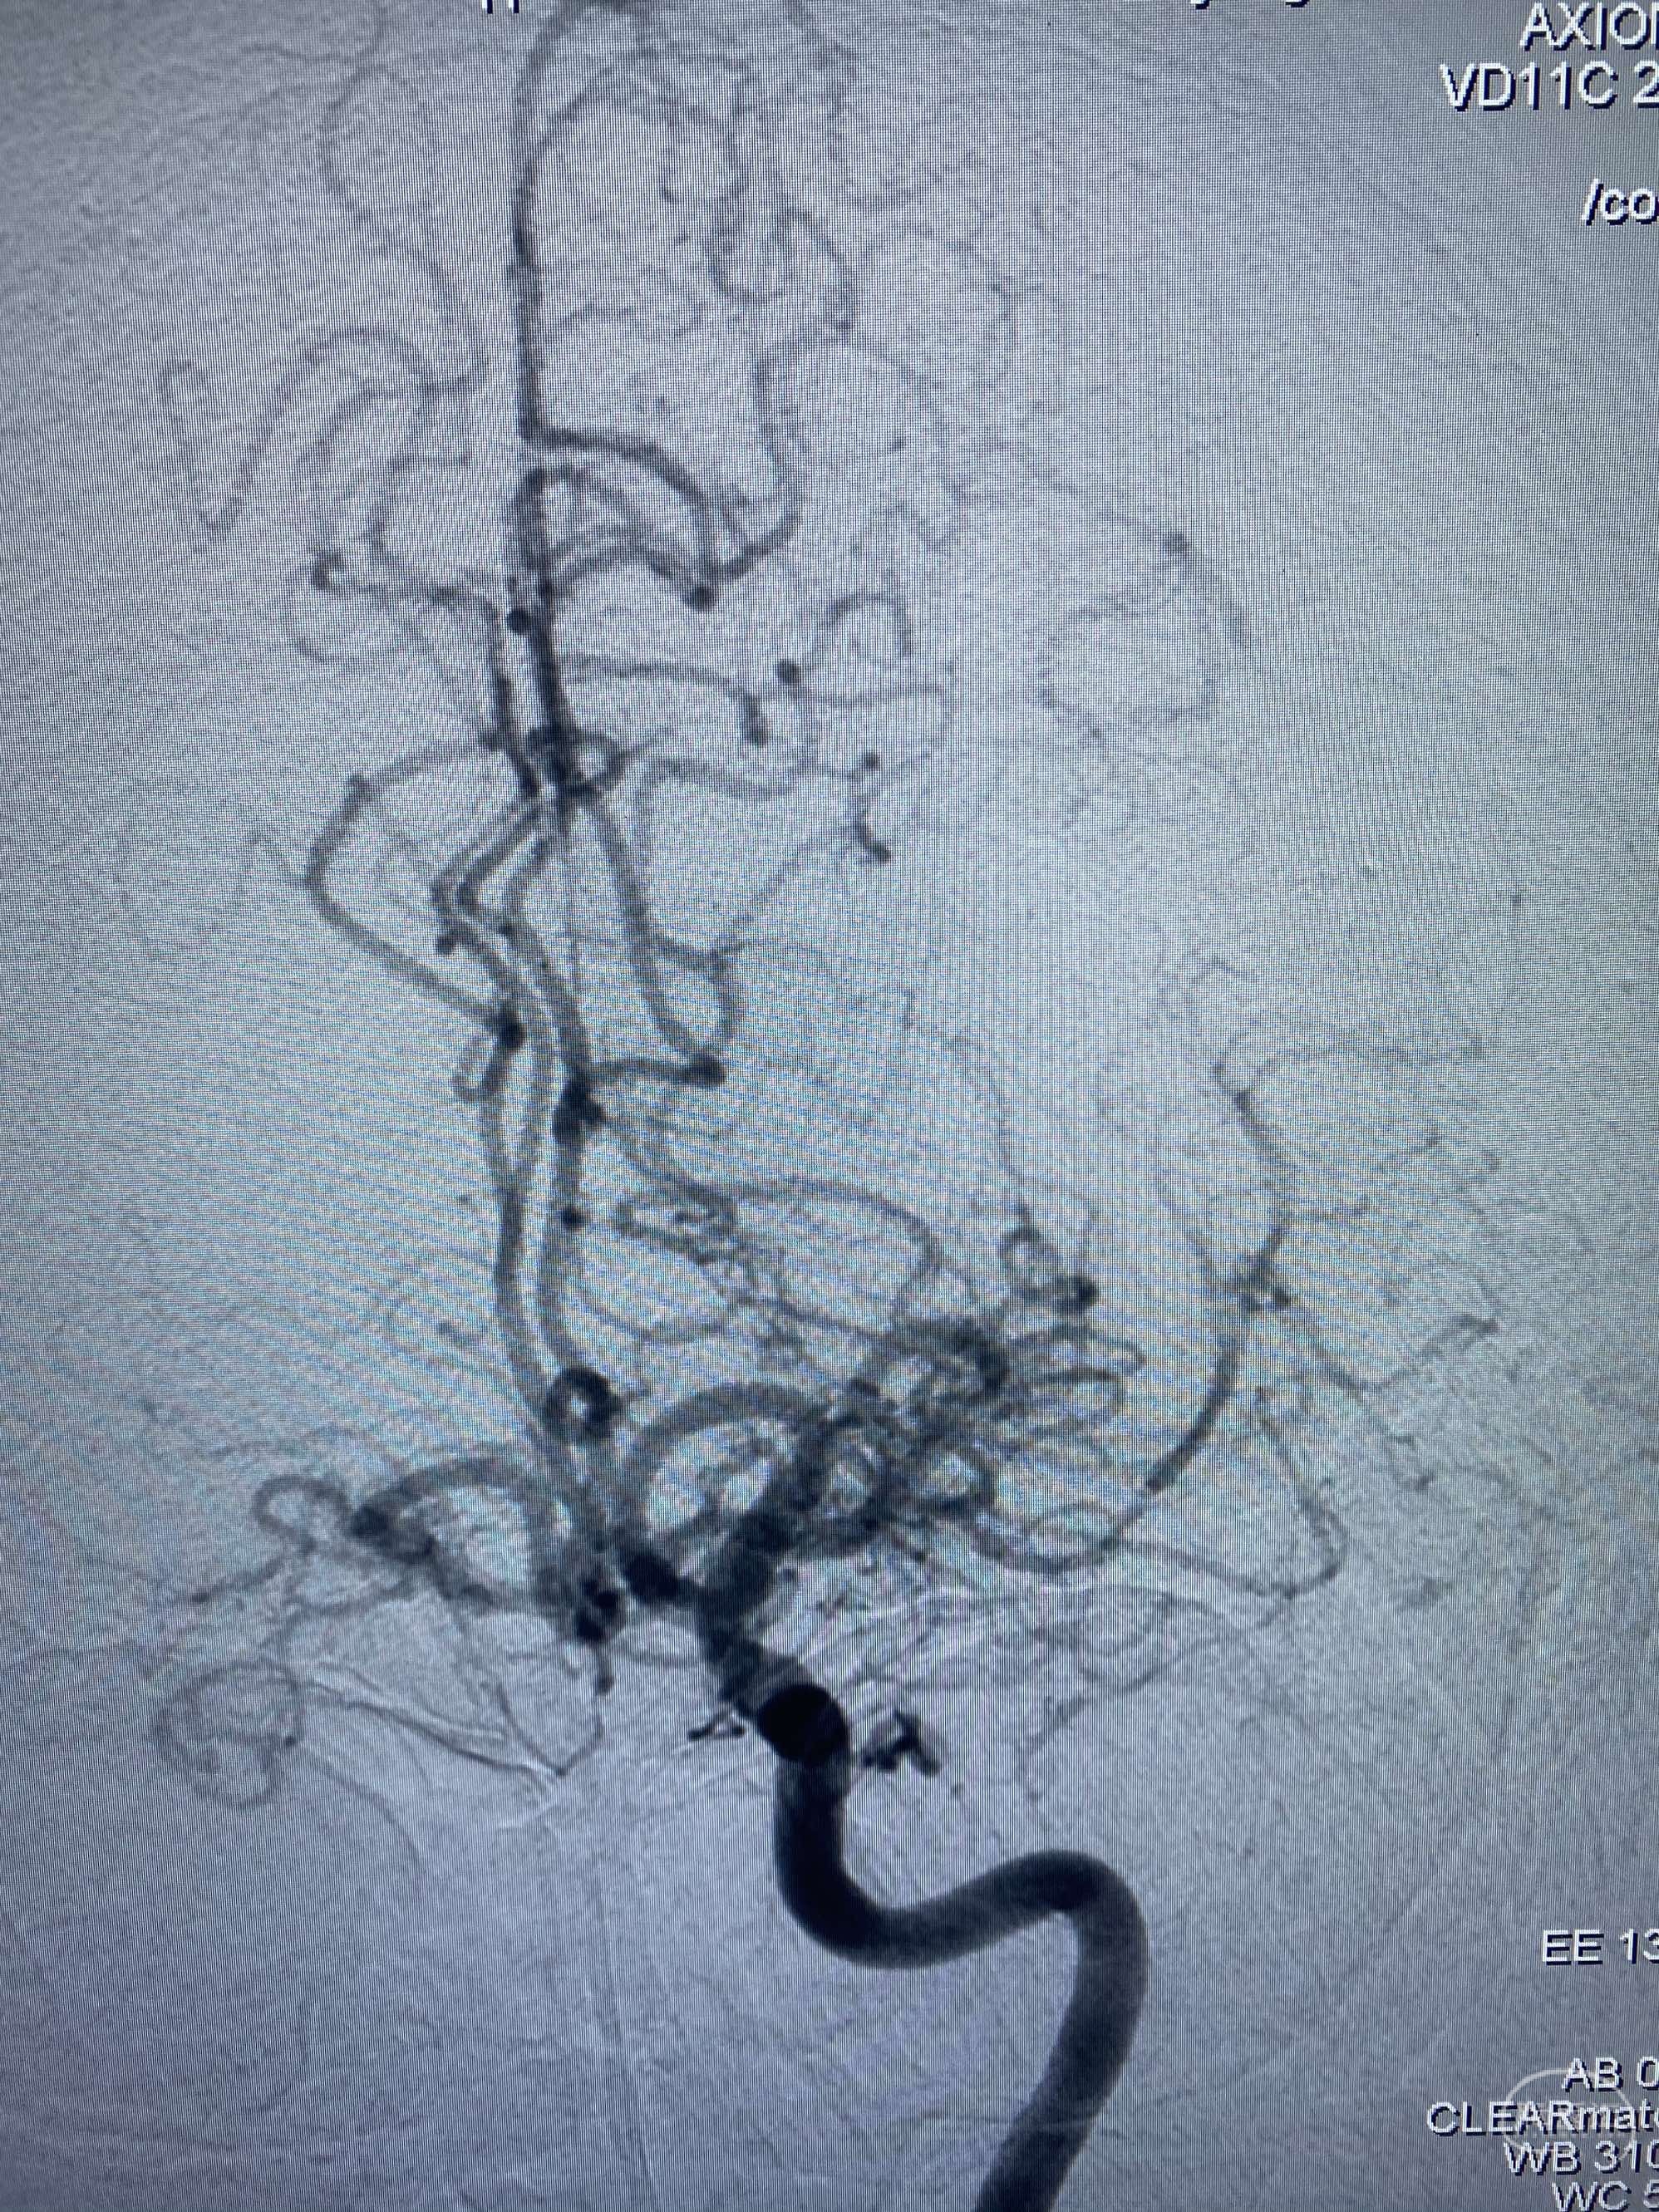

MLS,M79Y,sah,双侧MCA烟雾病,Heubner返动脉瘤,前交通段开窗,细支发出Heubner返动脉,瘤颈细长,瘤颈口比微导管细,弹簧圈2mmx3cm“隔山打牛”填塞治愈,Heubner返动脉保留。

该患者术后2天观察神志清楚,四肢活动正常。

Heubner返动脉是由大脑前动脉A1末端发出的豆纹动脉,由于走形和A1段相反,故称Heubner返动脉,该动脉梗塞可能引起尾状核头梗塞,引起偏瘫和面瘫,便身震颤等症状。